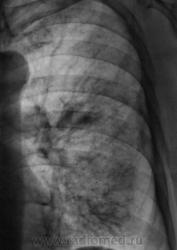

При расшифровке флюорограмм пациент "взят на контроль". Жалоб пациент не предъявляет. Подняли "архив", флюорограмма за 2009 г. - "норма".

Произвели стандартное дообследование.

Томограммы.